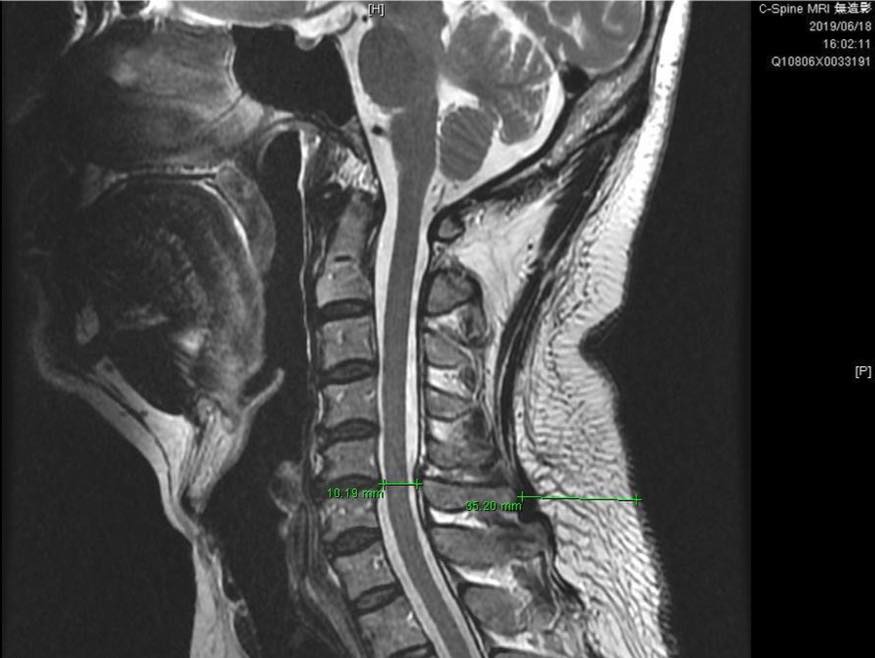

個案為台北市五十多歲的林先生,長期偏頭痛、頭暈、焦慮、恐慌、胸悶、睡眠障礙、腰背痠痛、胃酸逆流、脹氣,拿了2019/5拍的頸椎的MRI 與腰椎MRI來看,發現腰椎完全沒有任何問題!但就是很長期的腰酸背痛,頸椎也只有看到一點輕微的壓迫,可是症狀怎麼會那麼嚴重!!